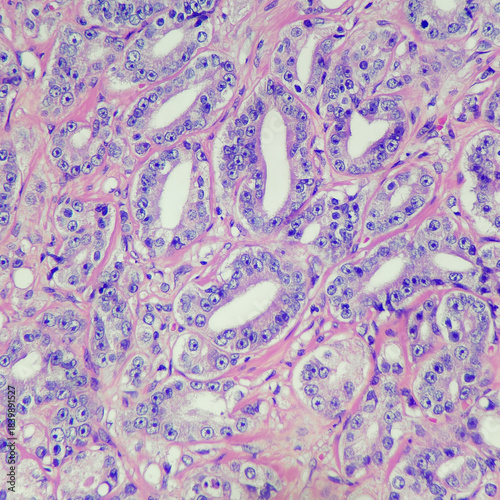

Mikrofotografi - Plakater, Poster, Billeder på lærred